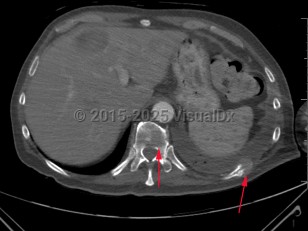

Pathologic fracture

A fracture that occurs from an underlying disease process that has weakened the bone, eg, cancer metastasis to bone, bone cysts, Paget disease, hyperparathyroidism, and osteoporosis. Pathologic fractures typically present with severe, localized pain after a very mild traumatic event, although they can occur with no trauma. Vertebrae and proximal long bones are the most common sites for pathologic fractures.

Pathologic fractures are sometimes the first presenting symptom of malignancy, though they most often occur in patients with a known primary cancer. Most pathologic fractures will require surgical intervention. Pathologic fractures due to malignancy are typically also treated with chemotherapy or radiation.